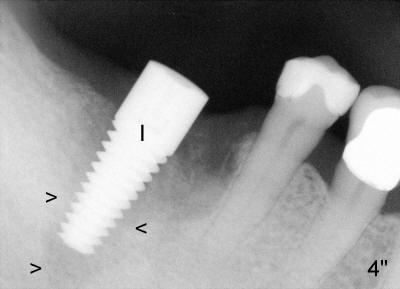

In case that there is an oral infection, submerged implant (Fig.4: I; Bicon 5x8; white line indicates gingival margin) may reduce the chance of pathogen contamination postoperatively. Fig.5 shows slight wound gaping after suture removal, one week postoperatively. In contrast, the implant in Fig.4' (Tatum 6x17) is non-submerged (white line indicates gingival margin). Two week post-operatively, an infection develops buccal to the implant (Fig.5'). Bone loses around the non-submerged implant 1 month after placement (Fig.4"). Finally the implant has to be removed. Return How to Avoid Post-implant Infection